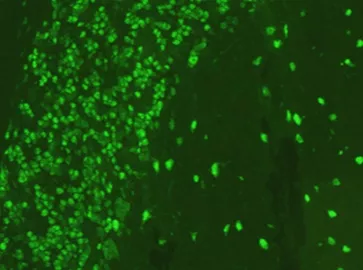

• Антитела к клеткам Пуркинье мозжечка

Антитела к клеткам Пуркинье мозжечка

Характеризуется специфическим свечением цитоплазмы клеток Пуркинье и/или их дендритных отростков и встречается у пациентов при выявлении анти-Yo (PCA-1), PCA-2, анти-Tr (Dner), анти-CARP (anti-carbonic anhydrase-related protein VIII), Anti-ITPR1 (Anti-Sj) антител.

• Выявление свечения клеток Пуркинье чаще всего встречается у пациентов с подострой дегенерацией мозжечка в сочетании с дизартрией и мозжечковой атаксией, у пациентов с лимбическим энцефалитом, миастенией Ламбертона-Итона, автономной нейропатией, моторной нейропатией, а также с лимфомой Ходжкина. Данные антитела могут быть ассоциированы с такими заболеваниями, как мелкоклеточная карцинома легких, новообразования яичников, карцинома молочной железы, карцинома матки и меланома. Данный тип свечения наиболее часто встречается при наличии anti-Yo антител.